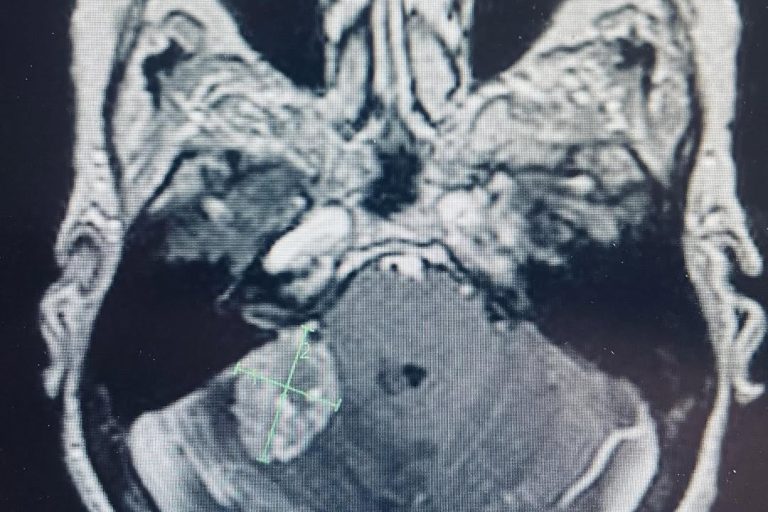

Meet Lin Sanders—a true inspiration of resilience and determination! Part 1 Lin underwent a complex two-level lumbar fusion at Texas Neuro-Spine Surgery. The procedure involved an anterior lumbar interbody fusion (ALIF) at L3-4 and L4-5, followed by laminectomies and pedicle screw instrumentation at the same levels. These surgeries were performed to help address her back…